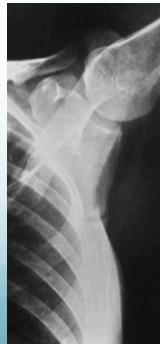

Characteristic Sign: Looser’s Zones

- Poorly healing stress fractures typically occurring at:

- Neck of scapula

Looser’s zones Z are short lucent bands running through the cortex at right angles, usually going only part way across the bone